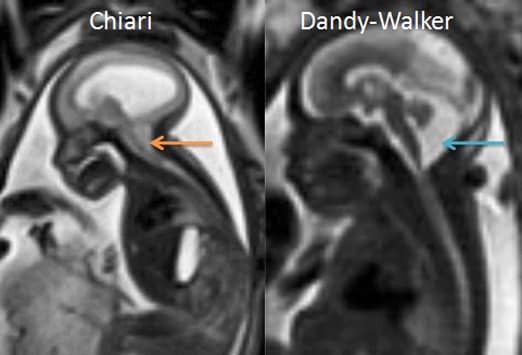

Аномалия Арнольда-Киари: MRI снимки